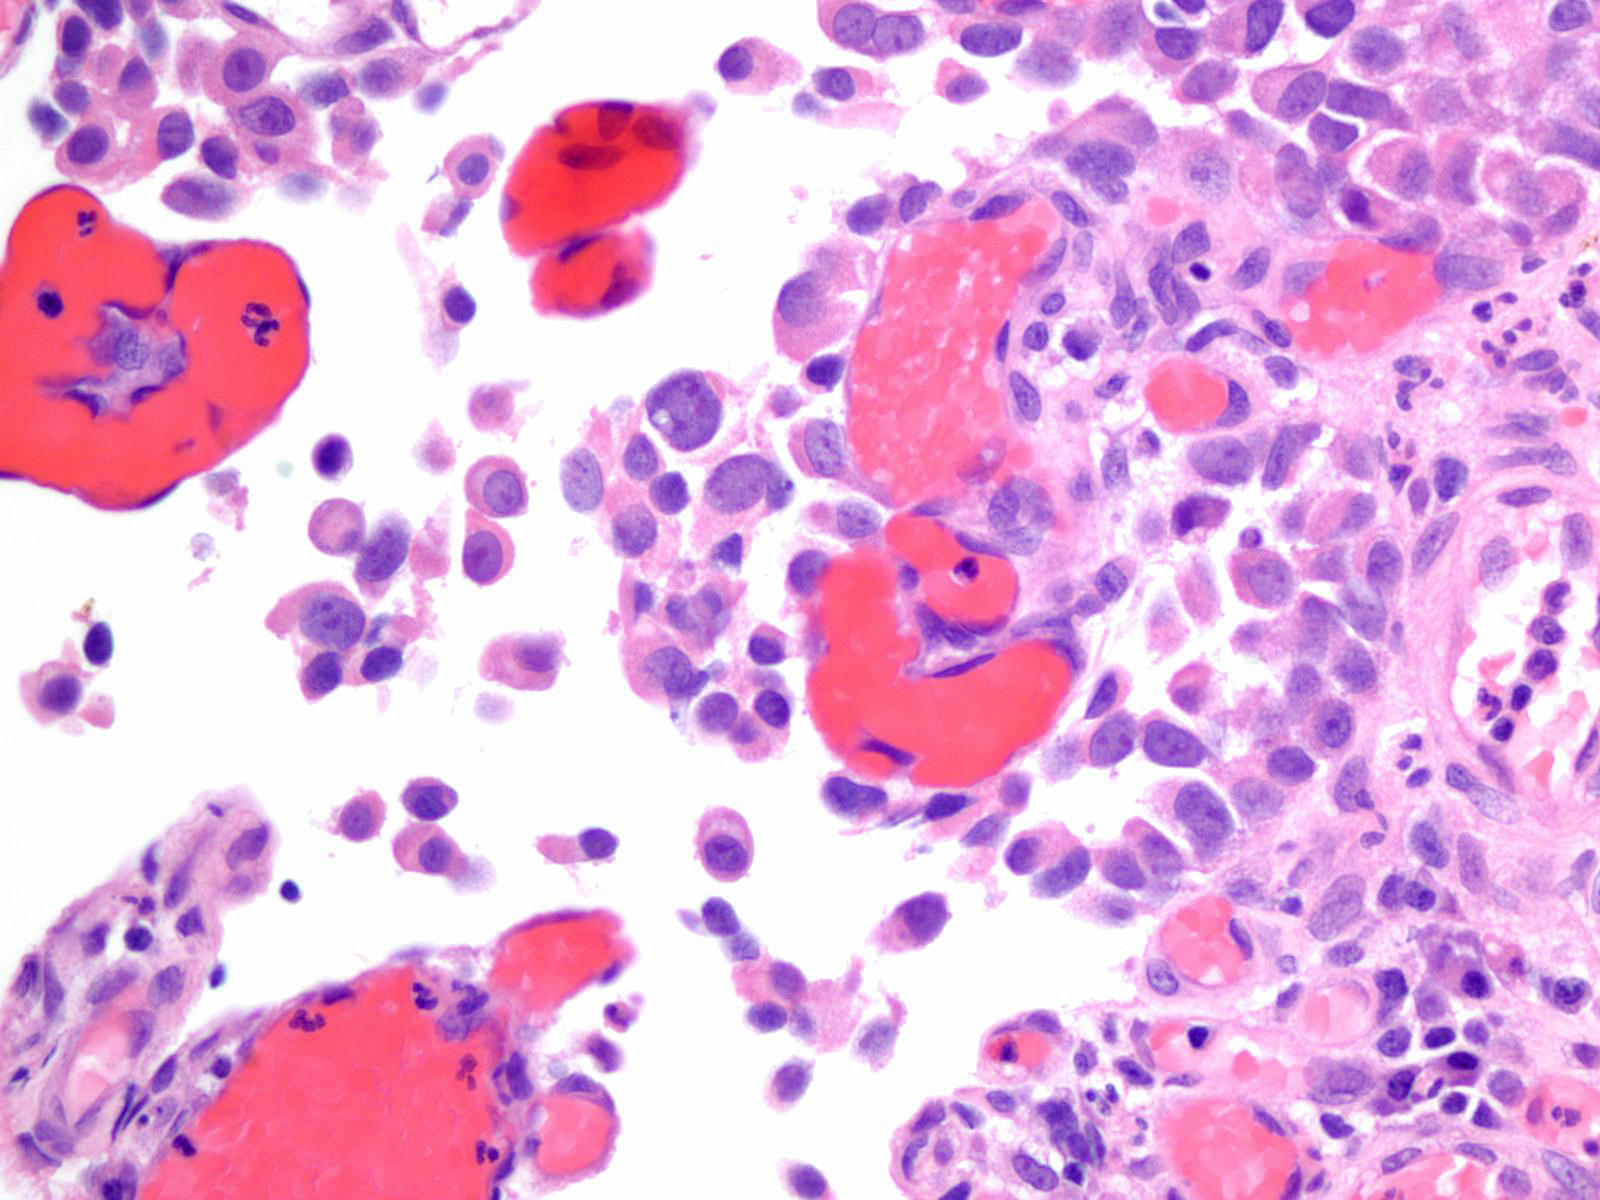

Consensus grade: High-grade papillary urothelial carcinoma (HG-PUC)

Case description (by case creator):

Lesion shows marked denudation. The cells lining the papillary fronds depict marked variation in nuclear size, shape and chromatin. Cells appear loosely cohesive and the architecture is disorganized.